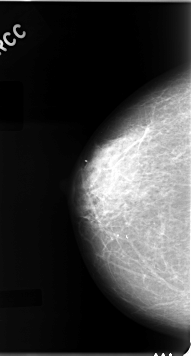

C_0050_1.RIGHT_MLO

RIGHT_CC LINES 4616 PIXELS_PER_LINE 2480 BITS_PER_PIXEL 12 RESOLUTION 50 NON_OVERLAY